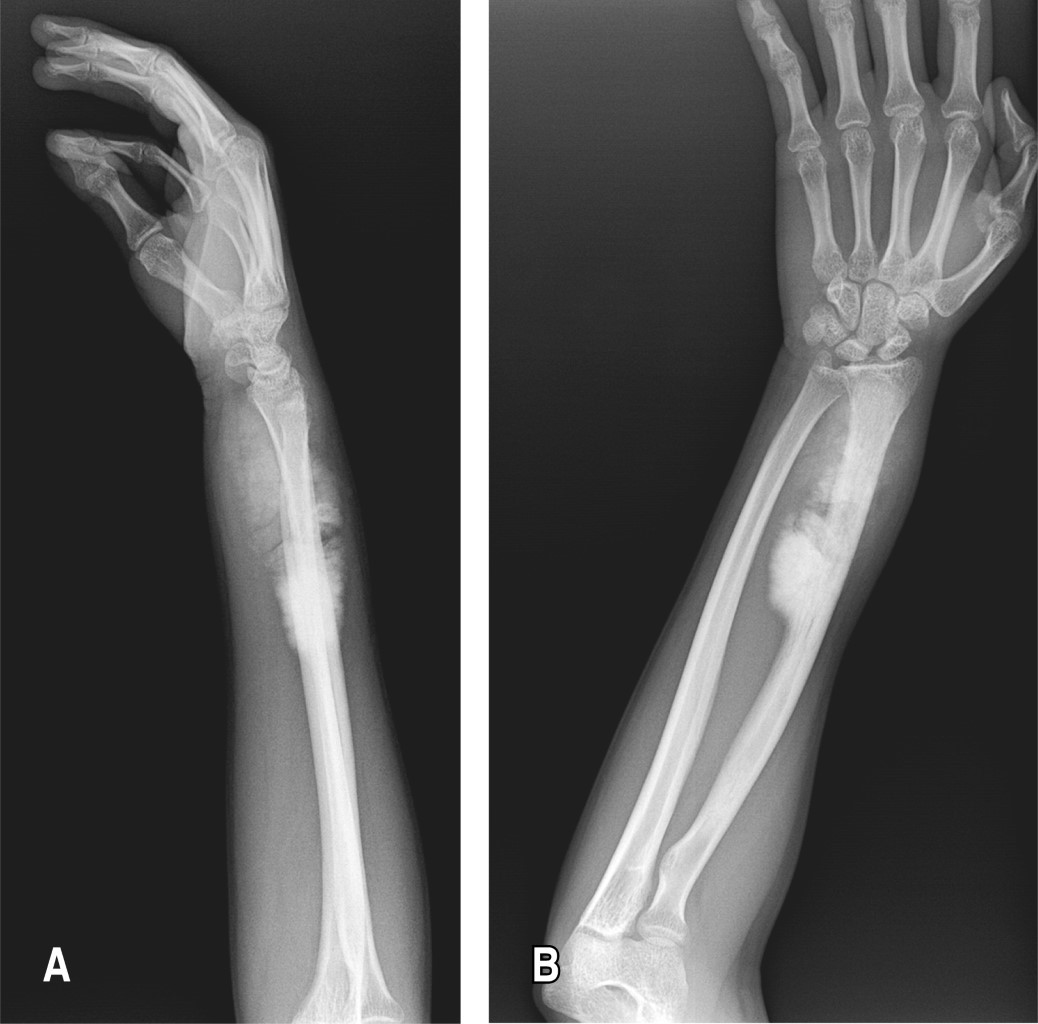

Posteriormente, es referido a la consulta de ortopedia en mayo de 2021 por presentar aumento de volumen a nivel del antebrazo, de crecimiento exponencial, presentando limitación a la pronosupinación, no a la flexoextensión, se solicitan radiografías anteroposterior y lateral de antebrazo, las cuales evidencian tumoración blástica, extracompartimental, excéntrica con reacción perióstica tipo triángulo de Codman de 11 × 5 × 4 cm (Figura 1). Se cita al paciente dos semanas después, con protocolo quirúrgico establecido se solicitan nuevas radiografías, encontrando aumento exponencial en tumoración, clínicamente dolor tumefacción, limitación de arcos de movilidad (Figura 2). Junio 2021. Se realiza biopsia escisional, mediante resección ampliada de radio derecho dejando márgenes de seguridad de aproximadamente 3 cm (Figura 3), exéresis de ganglio centinela y primera fila del carpo, centralización a tercer rayo de ulna y artrodesis con placa de reconstrucción de 18 orificios (Figura 4).